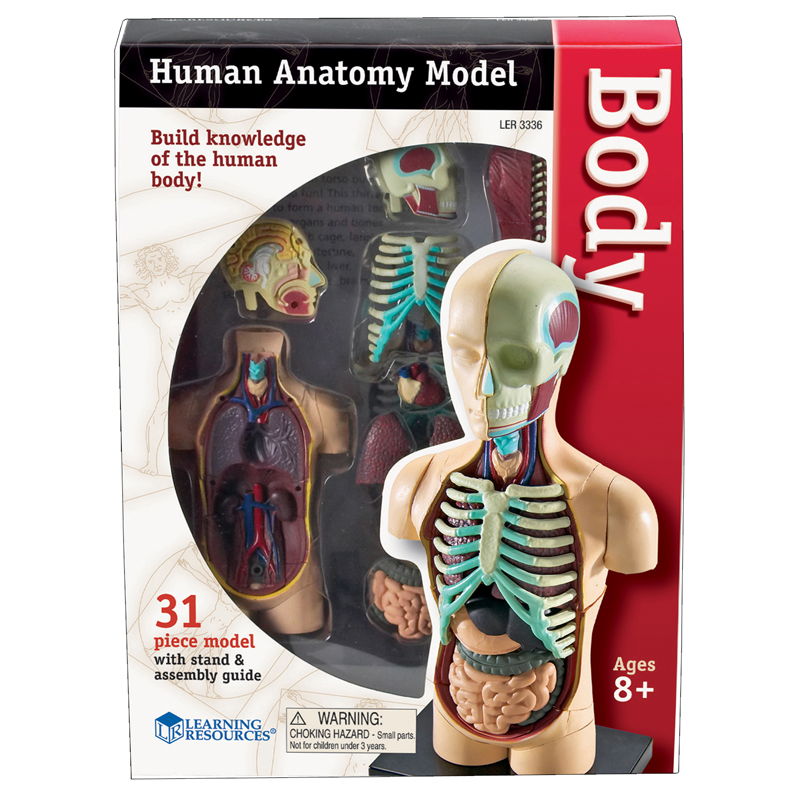

Product description

Hold these life-size human x-rays up to the light or use them on a light table and see every authentic detail of a real skeleton. Arrange the 18 pieces together to reproduce the entire body of a young adult 5' (1.5 m) tall. The teacher guide includes reproducible artwork and information on radiography. 18 pieces. Age 5+.

Human Anatomy

Human Anatomy